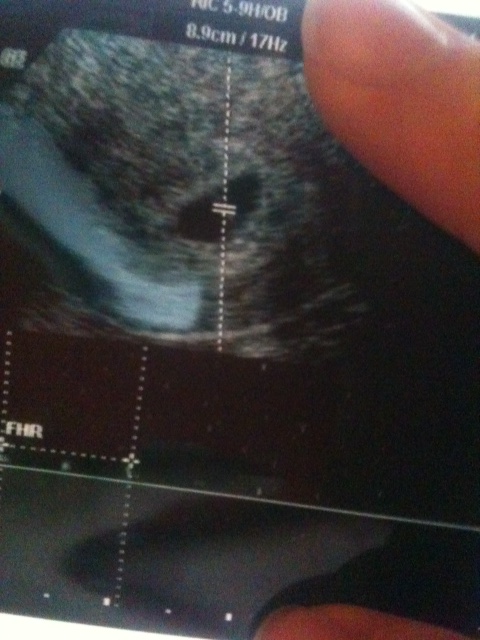

This trans-vaginal ultrasound was taken at exactly 6 weeks. I think I can faintly see the yolk sac on the right hand upper side. What do you think?

im intrested to see what people say about your because mine is all on the left side. if its a vaginal u/s does that mean its flipped or not? i think with vaginal what you see is what you get so i would lean boy for you and girl for me. but again im new to all this and im not sure. im just guessing. but i also read upper means girl and lower means boy. so maybe its a girl, im sorry im pretty much useless when it comes to ramzi.

it's hard to say what side it is on because whether you get a transvaginal u/s a not, the tech can flip things on the screen with a press of a button.

I went in for an u/s at 5 wks 4 days and the baby was on the left (transvag) then at 5 weeks 6 days, another u/s, and baby was on the right (transvag). So, one of the techs flipped, but I don't know which one.

Really the only way to know for sure is to ask the tech is the placenta is on the right or left.